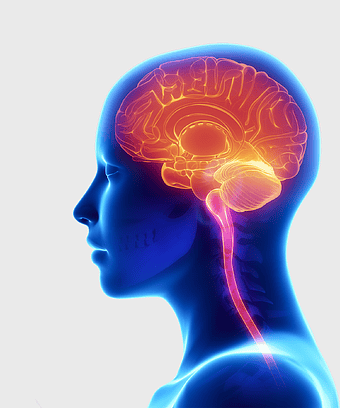

Human brain injury, brain damage disease, neuron network, neuroplasticity recovery, cerebral health, neurological disorders, brain anatomy illustration -